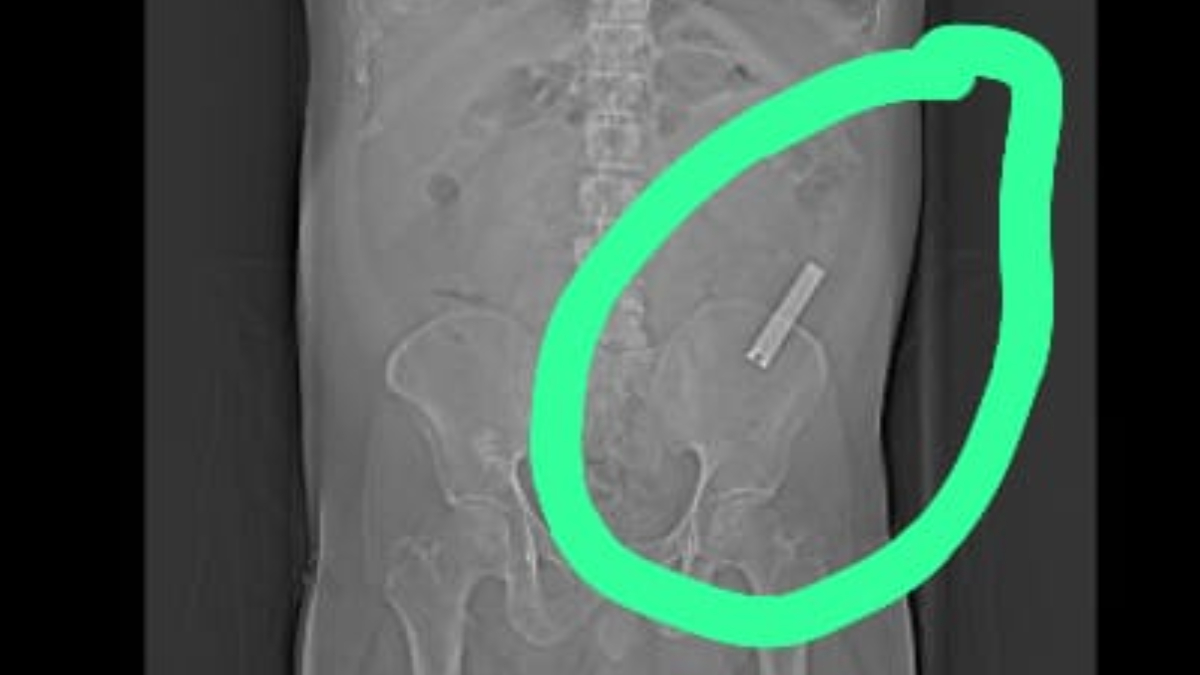

ಈ ವ್ಯಕ್ತಿ ನೈಲ್ ಕಟ್ಟರ್ ನುಂಗಿ 8 ವರ್ಷ ಆದರೂ ಕೂಡ ಆತನಿಗೆ ಆಗೆಲ್ಲ ಏನೂ ನೋವು ಕಾಣಿಸಿ ಕೊಳ್ಳುತ್ತಾ ಇರಲಿಲ್ಲ. ತೀರಾ ಇತ್ತೀಚೆಗೆ ಈತನಿಗೆ ಹೊಟ್ಟೆ ನೋವು ಕಾಣಿಸಿ ಕೊಳ್ಳುತ್ತದೆ, ಕೂಡಲೇ, ಆ ವ್ಯಕ್ತಿಯನ್ನು ಸ್ಥಳೀಯ ಆಸ್ಪತ್ರೆಗೆ ತೋರಿಸುತ್ತಾರೆ. ಆಗ ಸ್ಕ್ಯಾನಿಂಗ್ ಮಾಡೋದಕ್ಕೆ ಡಾಕ್ಟರ್ ಸಲಹೆ ಕೊಡುತ್ತಾರೆ.

ಬಳಿಕ ಈತನ ದೇಹದಲ್ಲಿ ನೈಲ್ ಕಟ್ಟರ್ ಇರೋದು ಗೊತ್ತಾಗುತ್ತೆ. ತಕ್ಷಣ ಆತನನ್ನು ಮಣಿಪಾಲ್ ಆಸ್ಪತ್ರೆಗೆ ದಾಖಲು ಮಾಡಲಾಗುತ್ತೆ. ಬಳಿಕ ವ್ಯಕ್ತಿಯ ಆರೋಗ್ಯ ಸ್ಥಿತಿ ಗಮನದಲ್ಲಿ ಇಟ್ಟುಕೊಂಡು ವೈದ್ಯರು ಆತನಿಗೆ ಶಸ್ತ್ರ ಚಿಕಿತ್ಸೆ ಮಾಡುತ್ತಾರೆ. ಆ ಚಿಕಿತ್ಸೆ ಯಶಸ್ವಿ ಆಗುತ್ತೆ, ಕೊನೆಗೆ ಈಗ ಆ ವ್ಯಕ್ತಿ ಡಿಸ್ಚಾರ್ಜ್ ಕೂಡ ಆಗಿ ಮನೆ ಸೇರಿದ್ದಾರೆ.

ಪಾನಮತ್ತನಾದ ವ್ಯಕ್ತಿ ನೈಲ್ ಕಟ್ಟರ್ ನುಂಗಿ ಸುಮಾರು 8 ವರ್ಷವೇ ಕಳೆದು ಹೋಗಿದೆ. ಆ ನೈಲ್ ಕಟ್ಟರ್ ಅನ್ನ ಮಣಿಪಾಲ್ ಆಸ್ಪತ್ರೆಯ ವೈದ್ಯರು ಈಗ ಹೊರ ತೆಗೆದು ಯಶಸ್ವಿ ಚಿಕಿತ್ಸೆ ನಡೆಸಿದ್ದಾರೆ. ಹೀಗಾಗಿ ವೈದ್ಯರ ಕೈ ಚಳಕದ ಬಗ್ಗೆ ಸದ್ಯ ಚರ್ಚೆ ಆಗುತ್ತಿದೆ. 8 ವರ್ಷಗಳಿಂದ ಹೊಟ್ಟೆಯಲ್ಲಿ ಇದ್ದ ನೈಲ್ ಕಟ್ಟರ್ ವೈದ್ಯರು ಹೇಗಪ್ಪಾ ತೆಗೆದರು ಅಂತ ಜನ ಬಾಯಿ ಮೇಲೆ ಬೆರಳಿಟ್ಟು ಯೋಚನೆ ಮಾಡುತ್ತಾ ಇದ್ದಾರೆ.